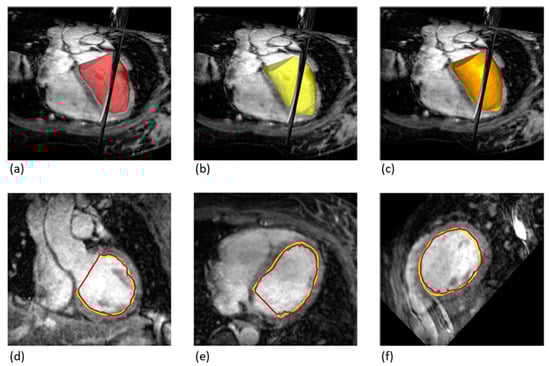

Figure 1. Approach for generating LV volumes from 2D-cine and 3D-wh sequences. (a) Generation of LV volumes in 2D-cine: acquiring stacks of cross-sectional images at different phases of the cardiac cycle. Due to heart motion, cardiac base and apex are not captured (2D-cine-lost). In contrast, 3D-wh imaging acquires the entire heart volume. (b) The individual cross-sectional images are synchronized according to the cardiac phase, representing end-systole and end-diastole. (c) Interpolation leads to the creation of a combined cylindrical volume in 2D-cine, where the volume of the papillary muscles (papillary-3D-wh) is included. The 3D-wh segmented volume, on the other hand, is comprehensive and does not contain papillary muscle volume. (d) Construction of corrected volumes: 2D-cine adjust = 2D-cine—papillary-3D-wh + 2D-cine lost, 3D-wh-cylinder = 3D-wh—2D-cine lost.

A crucial point that has not been considered in the previous discussion is the fact that only the incomplete acquisition of the volume is possible through the 2D-cine technique [18,19]. Despite the good approximation of the actual morphology of the LV, the 2D-cine representation is also only an estimate of the three-dimensional shape of the LV based on the summation of the individual 2D layers [20]. The resulting cylinder does not fully take into account the edge structures at the cardiac base and apex (Figure 1c).

In isolated studies, it has already been shown that this image acquisition methodology is theoretically also suitable for performing LV volumetry, by creating two images; one in end-systole and one in end-diastole (Figure 1). Despite the theoretical superiority of this technique, a study by Goo et al. [14] could not demonstrate a clear advantage over the 2D-cine technique. While the 3D-wh MRI proved extremely valid in the direct functional comparison with the PC-MRI, discrepancies in determining the volumetry from 2D-cine MRI could not be explained.

To enable a direct comparison of LV volumes between 2D-cine and 3D-wh, the 2D-cine volumes were transferred to the open-source software 3D Slicer. Using the segmentation workstation, summation calculations were performed based on the volume bodies: 2D-cine, 3D-wh and Papillary-3D-wh volumes. The derived volumes, 2D-cine-lost, 2D-cine-adjust, and 3D-wh-cylinder, were calculated for diastole and systole and visualized in the same 3D coordinate system (Figure 1). The volume 2D-cine-lost represents the volume parts at the base and apex that are not considered in the cylindrical form of the 2D-cine. The volume 2D-cine-adjust corrects the 2D-cine volumes by expanding the 2D-cine lost parts and subtracting the papillary volume. 3D-wh-cylinder was tailored to the cylindrical shape of the 2D-cine for direct comparison of the overlap using the Dice and Hausdorff metrics.

Figure 4. Comparison of Overlapping Volumes between 2D-cine and 3D-wh Techniques. (a) 3D Volume Reconstruction using 3D-wh (red), showing a reconstructed cylinder for direct comparison (3D-wh-cylinder). (b) 3D Volume Reconstruction using 2D-cine (yellow). (c) Merge of A and B, illustrating the degree of overlap between the 3D-wh and 2D-cine volumes. (df). Endocardial Overlapping in Different Slice Planes.